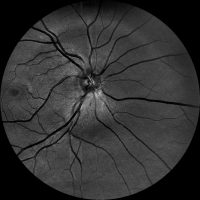

Dzięki technologi SLO – Scanning Laser Ophthalmoscope, podczerwieni oraz wiązki zielonego laseru, jesteśmy wstanie wykonać bardzo dokładny zrzut dna oka, dzięki czemu wykryjemy praktycznie każde zmiany w gałce ocznej. W realizacji takiego skanu nie potrzebne jest zakroplenie oka co znacznie usprawnia nam diagnostykę pod katem szybkości badania czy samopoczucia osoby poddanej tejże czynności. Badanie ma na celu wykrycie zmian w oku jak: jaskra, zaćma, zatory żylne, męty, retinopatie cukrzycową czy AMD(zwyrodnienie plamki żółtej), Pełna wizyta obejmuje:

– skanowanie laserowe dna oka,